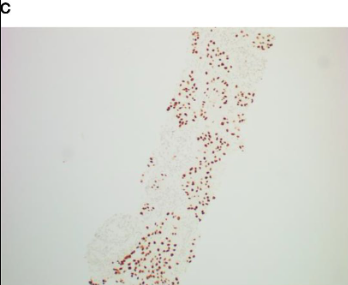

肺活检病理

肺腺癌(免疫组化:CK7+,NapsinA+,TTF-1+,CK5/6-,P40-,Ki-67阳性率约20%,CD56-)